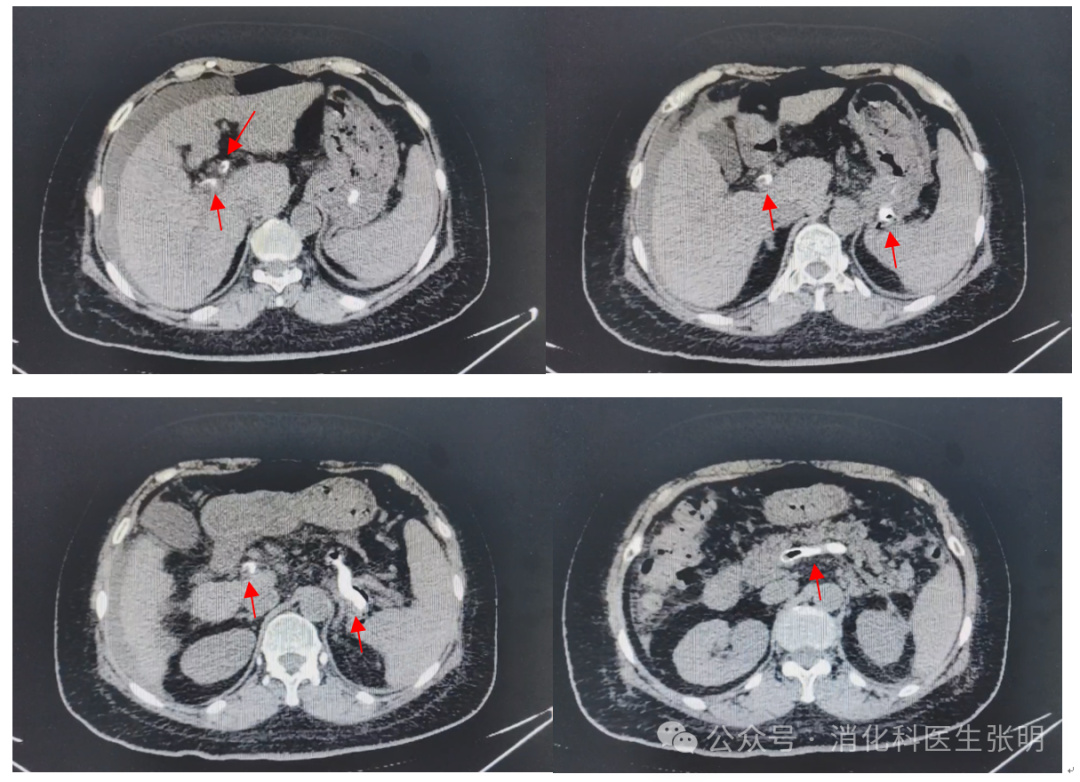

肝硬化门静脉血栓需要与非肝硬化门静脉血栓、肝硬化合并肝癌的门静脉癌栓,以及组织胶治疗后的门静脉胶栓相鉴别。

图片

连续4张图片,可以看到组织胶从胃底静脉经过脾静脉向门静脉主干和门静脉左右支延伸。